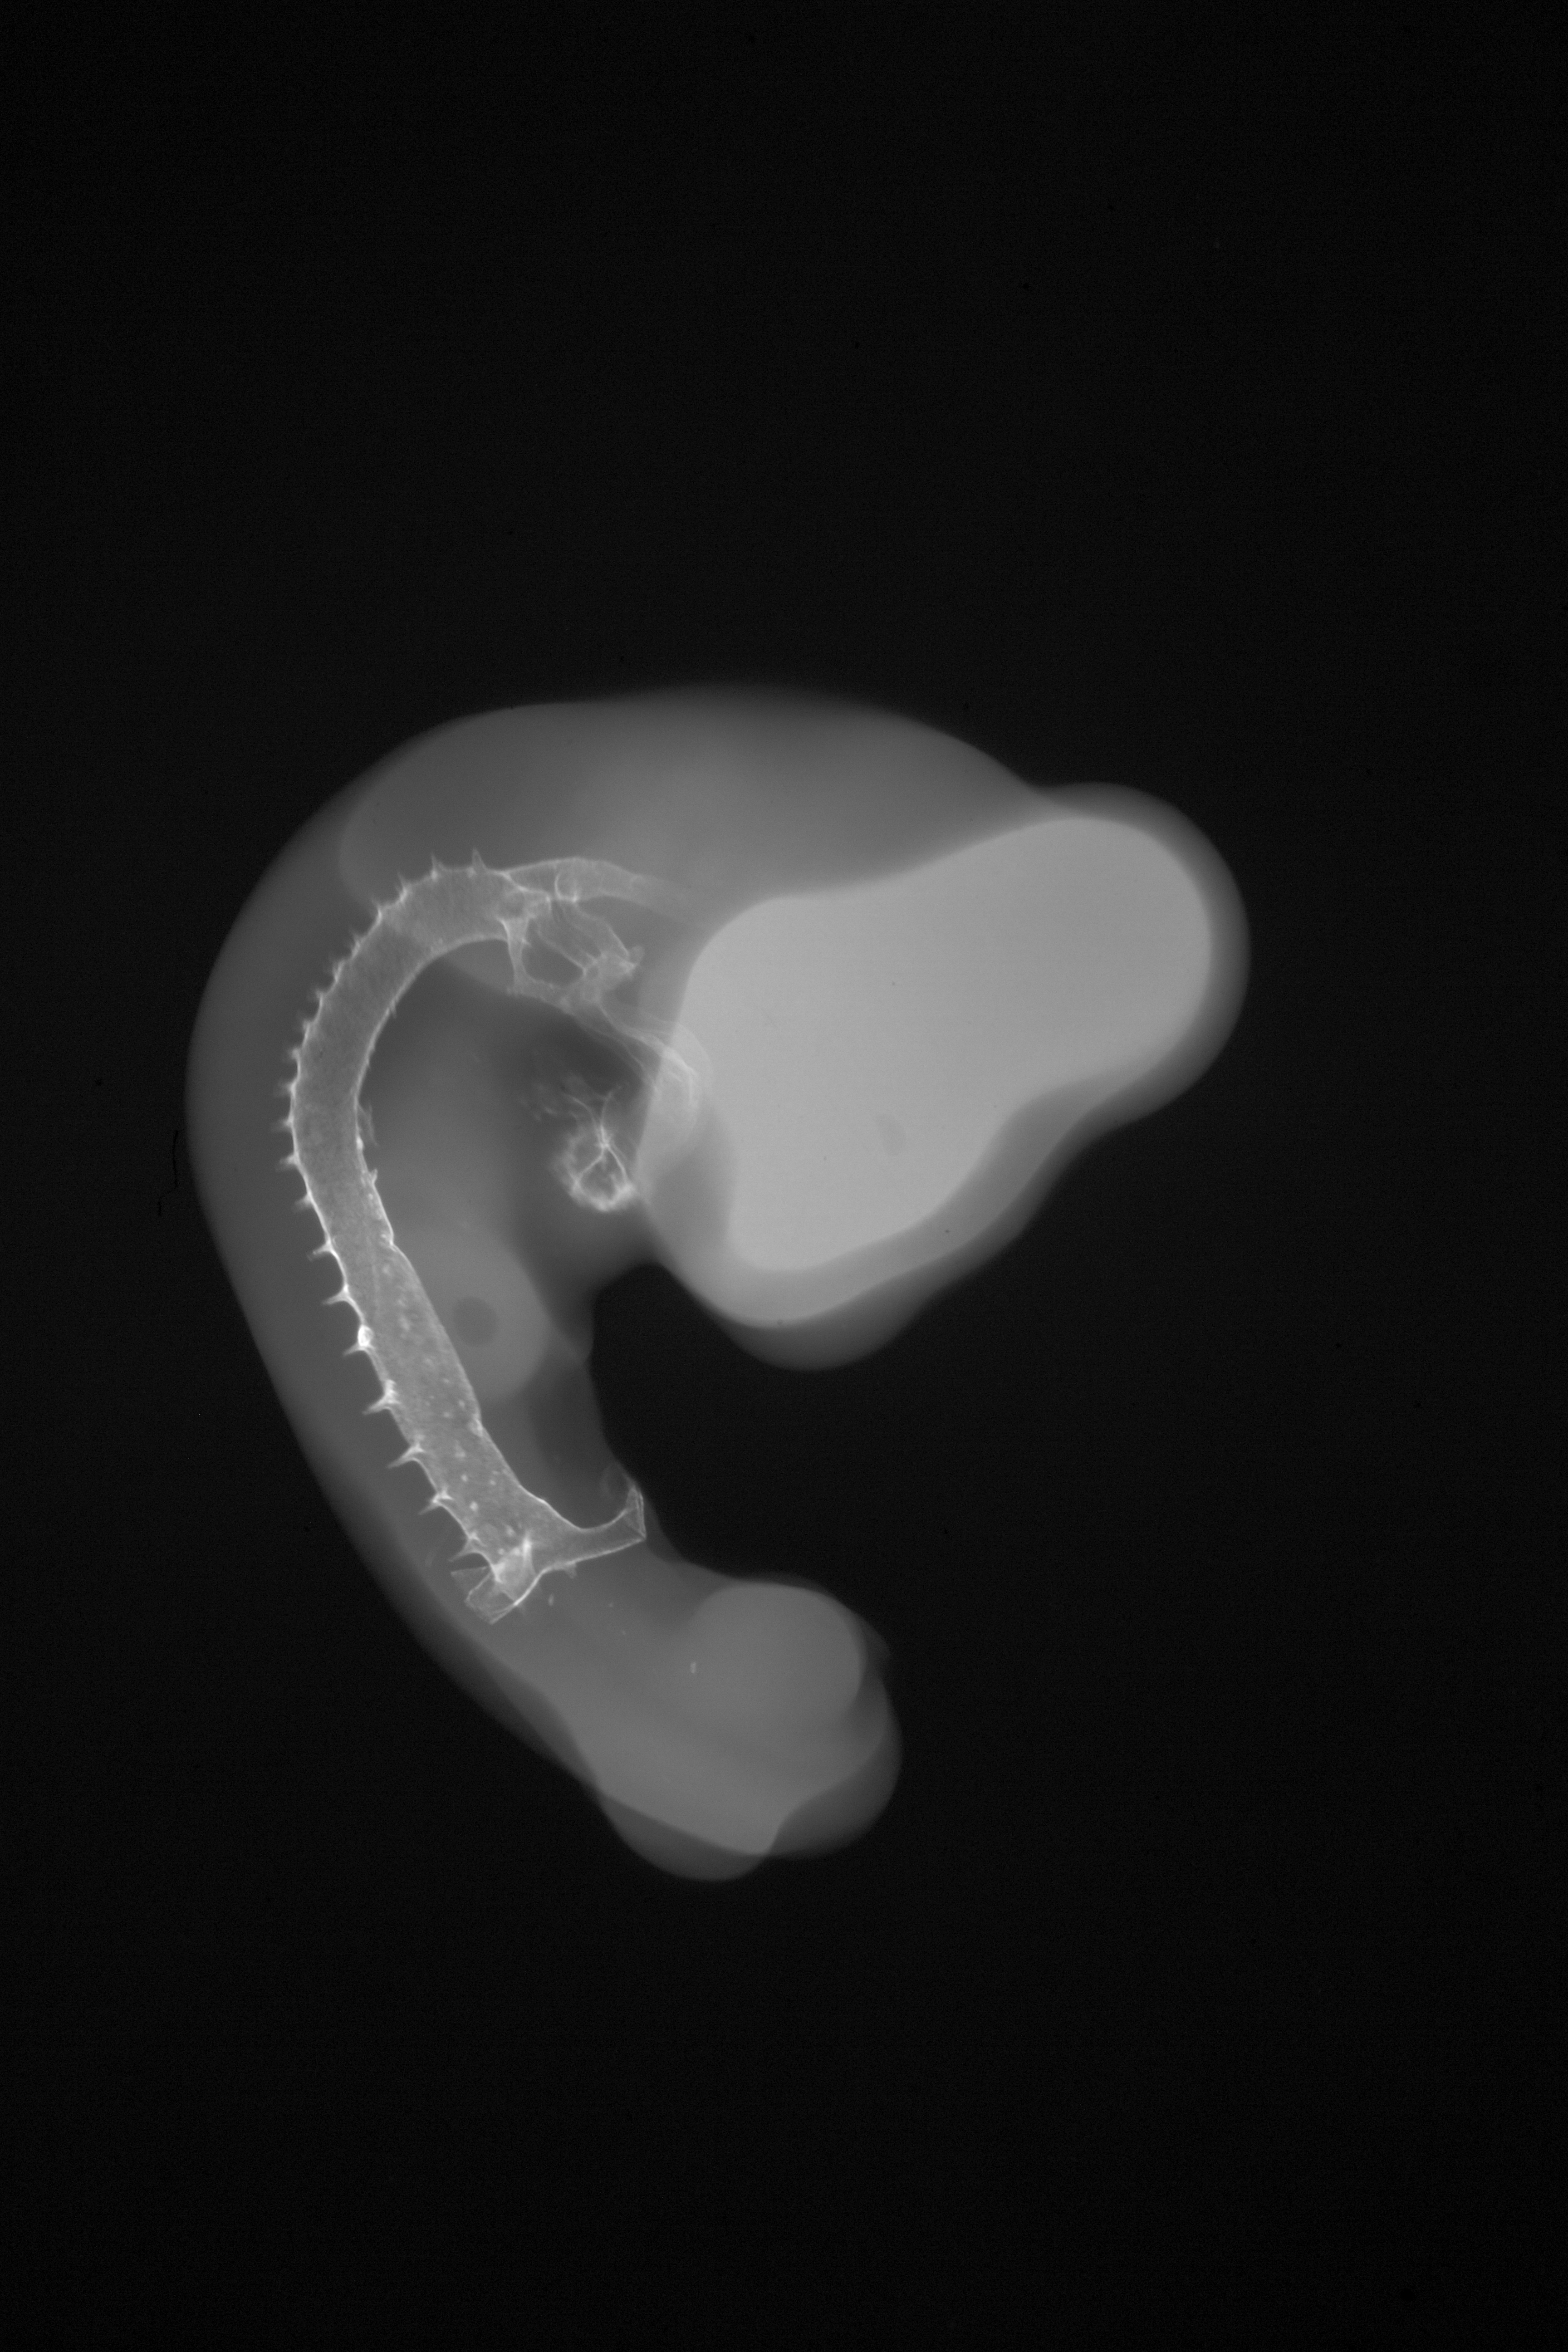

Chick Embryo Microangiography

Hamburger-Hamilton (HH) Stage 21 (approx. 3.5 days)

X-Ray Micrographs